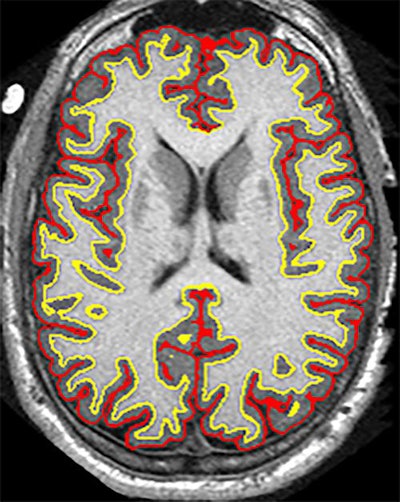

"There are two big messages for the radiological community. One is that whole-brain atrophy does appear to be a useful metric for phase II trials with progressive MS," said principal investigator Dr. Robert Fox, vice chair for research at the Neurological Institute at the Cleveland Clinic. "And, with diffusion-tensor imaging, magnetization transfer ratio, and optical coherence tomography, cortical thickness or cortical atrophy appears to be a robust measure of tissue injury, progression of that injury, and therapeutic response with ibudilast."

The researchers assessed each patient's clinical disability based on the Expanded Disability Status Scale (EDSS) every 24 weeks. At the same time, subjects underwent an MRI scan on a 3-tesla scanner (Magnetom Trio/Prisma or Skyra, Siemens Healthineers; or Excite 12x, GE Healthcare), as well as optical coherence tomography (OCT). Two independent readers evaluated the thickness of the retinal nerve-fiber layer on OCT and measured the rate of brain atrophy based on parenchymal fraction.

While all patients experienced atrophy, the brains of the patients with progressive MS in the placebo group shrank on average 2.5 mL more over two years than those in the ibudilast group, the researchers found. The rate of change in the brain parenchymal fraction was 0.0019 units of atrophy per year with the placebo, compared with 0.0010 units per year with ibudilast. That difference of 0.0009 was deemed statistically significant (p = 0.04).